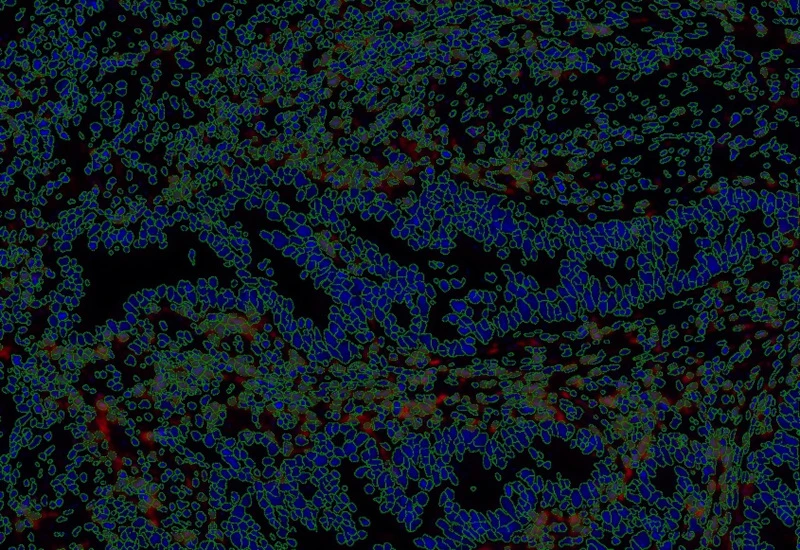

IF Immune status in situ

Characterize immune cell phenotypes relative to detected metastructures (e.g. tumors, glands), define distance ranges, measure cell-to-boundary distances inside/outside, and export up to 20 intensity, statistic, and morphometric parameters per cell compartment.

The IF Immune Status in Situ App provides phenotypic characterization of immune cells in reference to detected metastructures (e.g. tumors, glands) and measures the distance of detected cellular objects to the metastructure boundary (within and/or outside). Distance ranges can be defined. Each segmented cell compartment is measured for up to 20 intensity, statistic and morphometric parameters, as is the distance of each cell to the areas boundary.

Proximity measurements: 25-50µm